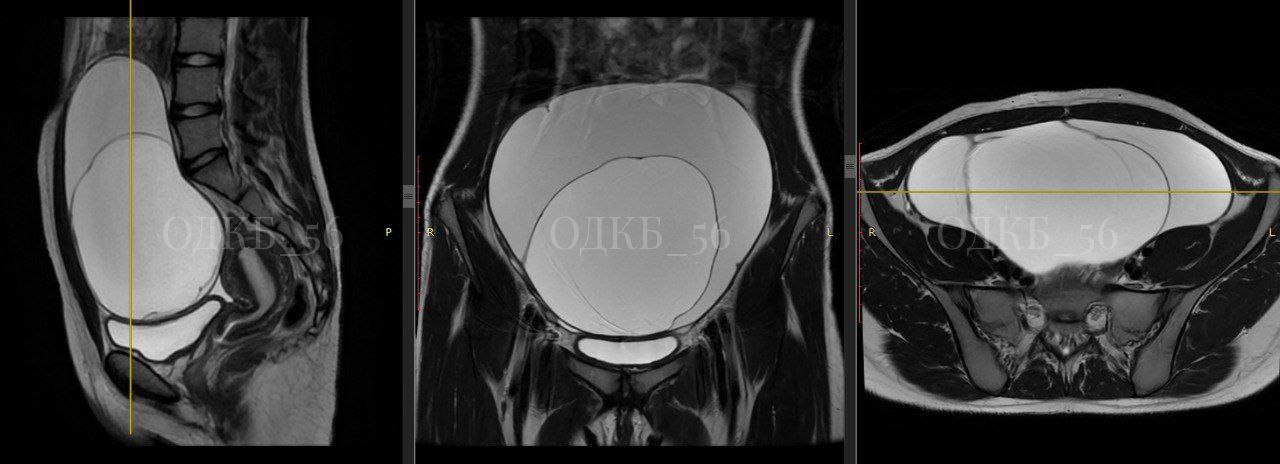

УЗИ и МРТ показало, что обнаружено объемное образование больших размеров. Было даже подозрение на злокачественную опухоль. Хирурги ОДКБ провели операцию.

— Образование, исходящее из правых придатков матки, размером 20 см в диаметре, было удалено в полном объеме, хотя было сложно, из-за выраженных спаечных процессов в малом тазу, — рассказали в ОДКБ.